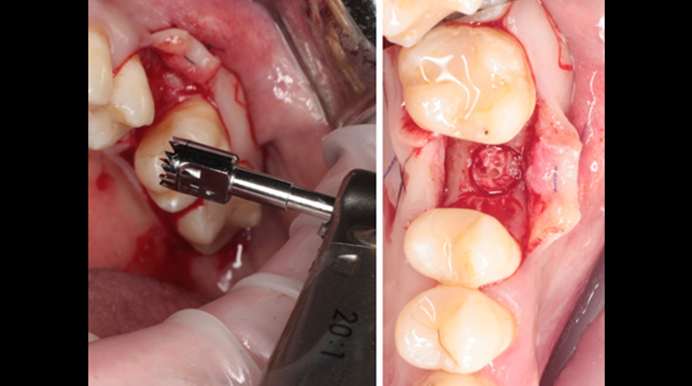

“Thin ridge expansion with minimally invasive surgery!

Use SmarThor & AnyRidge to place a wider diameter implant with minimal drilling after ridge splitting, even in thin ridge under 2mm! “

Clinical case: Ridge splitting technique using SmarThor + AnyRidge as expander

- Courtesy of Dr.Kwang-Bum Park, Korea -

Keywords

AnyRidge, ridge splitting, GBR, Dr. Kwang-Bum Park, mandibular posterior, SmartThor, Mega-Oss, thin ridge, bone regeneration

Products:

AnyRidge implant system. SmarThor, Mega-Oss